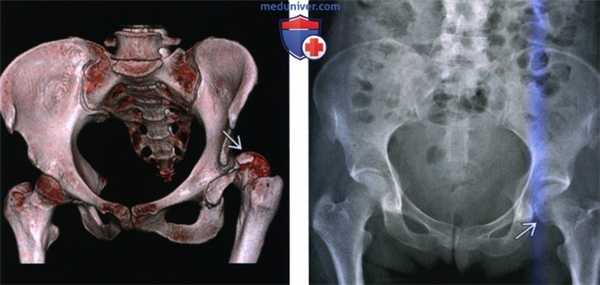

(Слева) КТ в передне-задней проекции, объемная 3D реконструкция: определяется задний вывих головки бедренной кости. КТ выполняется перед закрытой репозицией только если она оказалась неудачной. КТ позволяет оценить положение смещенных осколков, препятствующих репозиции.

(Справа) Рентгенография в передне-задней проекции, выполненная спустя год после заднего вывиха бедра: определяется латеральный подвывих левой головки бедренной кости и нарушение конгруэнтности сустава. Посттравматическая нестабильность бедра является известным, но плохо изученным феноменом.

(Справа) Рентгенография в передне-задней проекции: у пациента 25 лет, спустя год после заднего вывиха бедра, определяется остеофит, указывающий на ранний остеоартрит. Несмотря на то, что бедро было немедленно подвергнуто репозиции и фиксация перелома задней стенки была полностью анатомически правильная (с помощью длинной реконструктивной пластины и короткой трубчатой пластиной 1/3 длины), повреждение нижележащего хряща быстро привело к остеоартриту.